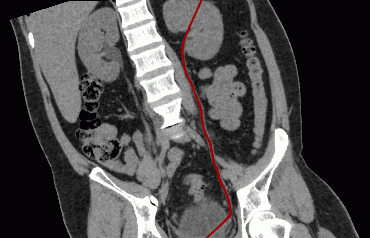

Fix the last point by left-clicking the mouse twice. While building the curve, the current section will be displayed in the bottom right-hand window. The other windows will display the projections of the curve on the corresponding planes (Fig. 5.8).

If necessary, correct the projections of the curve on the two other planes. For details on how to correct, see the section 5.7.4.